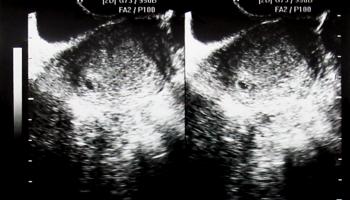

4. 임신 7주 차 - 하혈을 보았다.